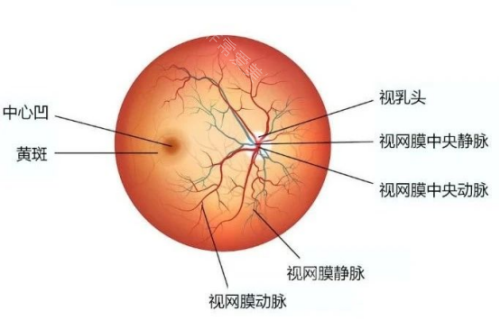

在探讨眼科疾病治疗时,眼底病的治疗备受关注,而武汉协和医院在这方面的表现值得深入了解。

在眼底病治疗方面,医生们能够运用可靠的技术和丰富的经验,为患者制定个性化的治疗方案。